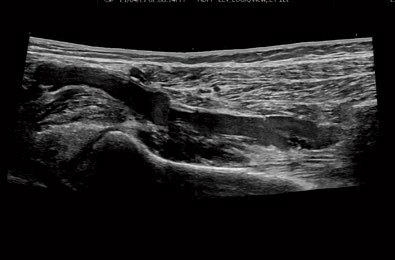

LOGIQ View

プローブを任意で動かすことで観察表示範囲を

広げる機能です。対象の広い部位、乳腺や

甲状腺全体、 四肢での観察に役に立ちます。